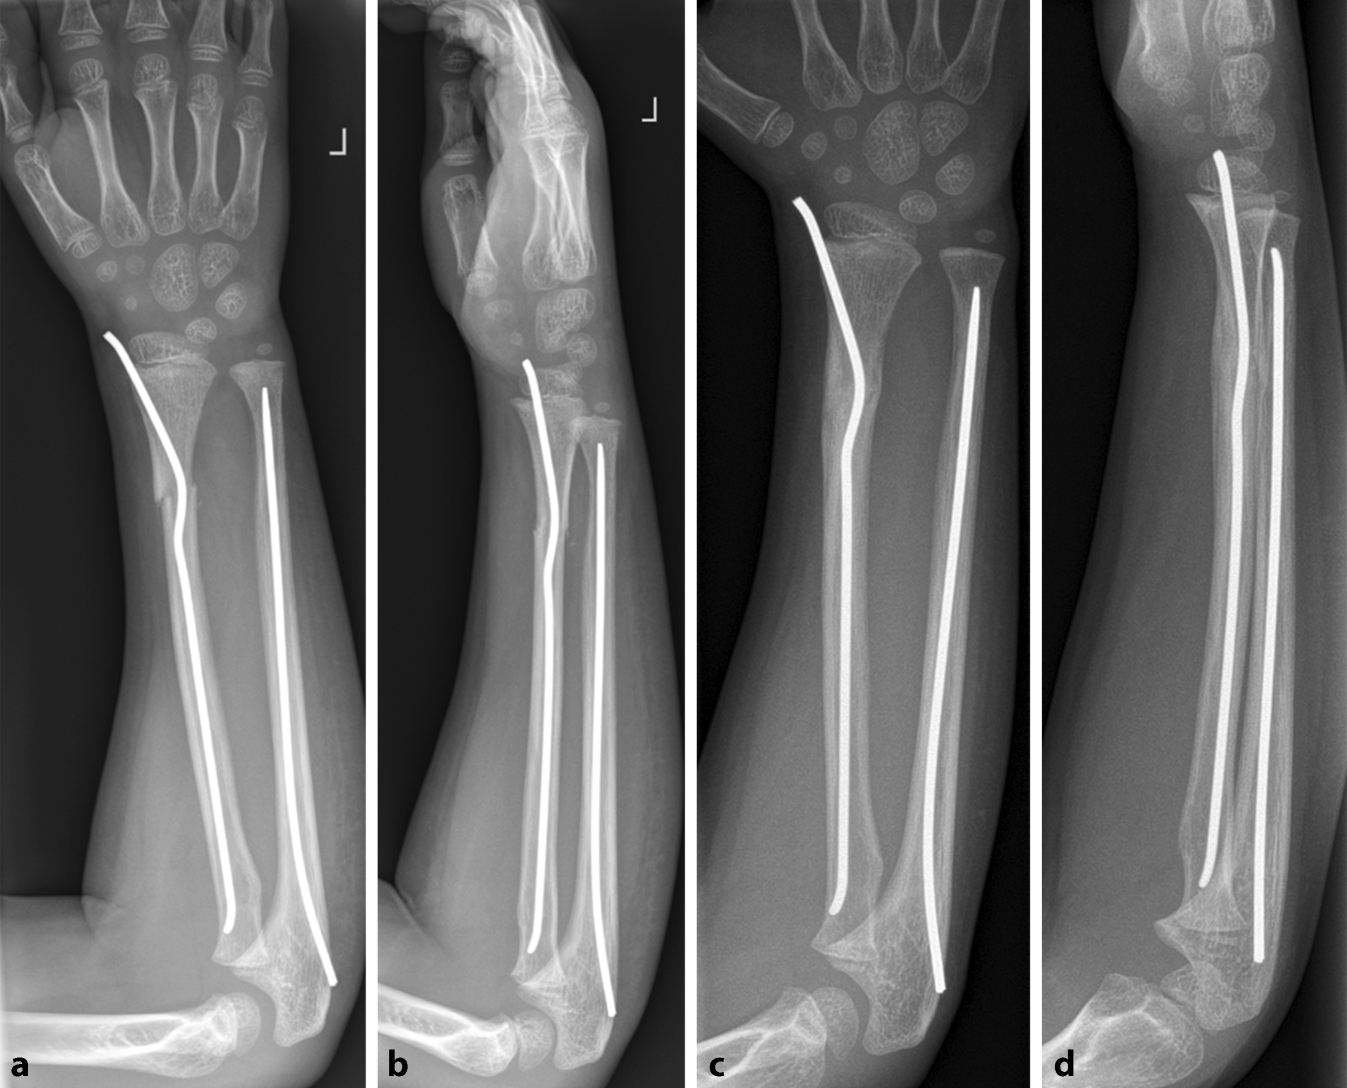

Abb. 13

Fallbeispiel. Versorgung einer diametaphysären Unterarmfraktur mit einem doppelt gebogenen TEN radial und antegradem TEN in der Ulna direkt postoperativ (a, b) und nach Konsolidierung (c, d)